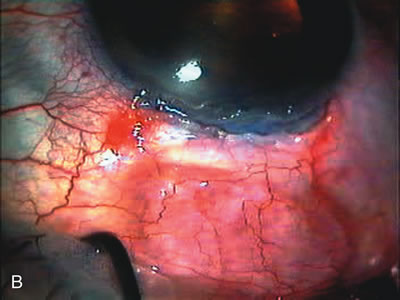

Fig. 3. Partial bleb failure following clear corneal phacoemulsification with foldable IOL. A. Preoperative bleb appearance prior to temporal lens extraction. Preoperative IOP was 12 mm Hg on no antiglaucoma medications. Time from 5-FU trabeculectomy surgery to lens extraction was one year. B. Bleb appearance 2 months after clear corneal cataract surgery with topical anesthesia. Following lens extraction, increased vascularity was noted along with decreased size of the filtering bleb. IOP increased to 20 mm Hg as early as 2 weeks after surgery, necessitating topical antiglaucoma therapy. C. High magnification view of bleb before lens extraction demonstrates diffuse pale bleb. D. High magnification view of bleb 2 months after surgery. There are vessels surrounding the nasal side of the bleb and the overall bleb size is smaller.